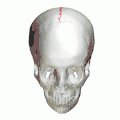

![]() Human adult skull from above | |

Animation. Sagittal suture shown in red. -

Sagittal suture seen from inside.